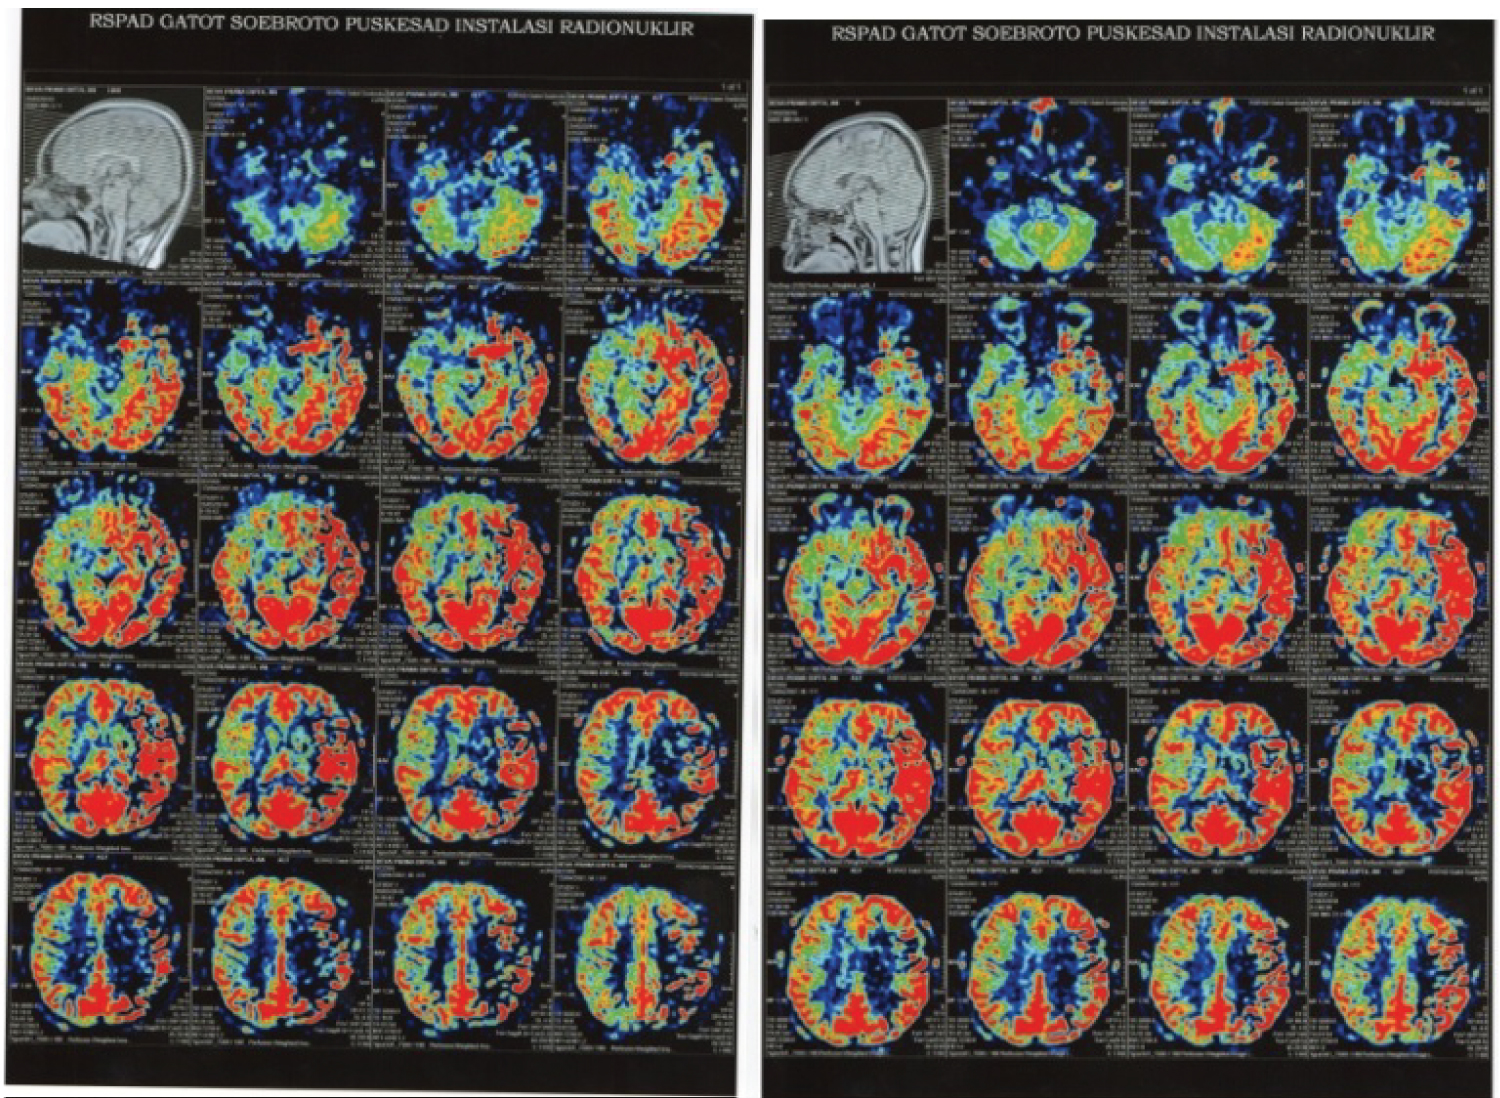

Figure 3: The perfusion image compared brain perfusion before (left) and after (right) IAHF. There is progression CBF after IAHF procedure. View Figure 3